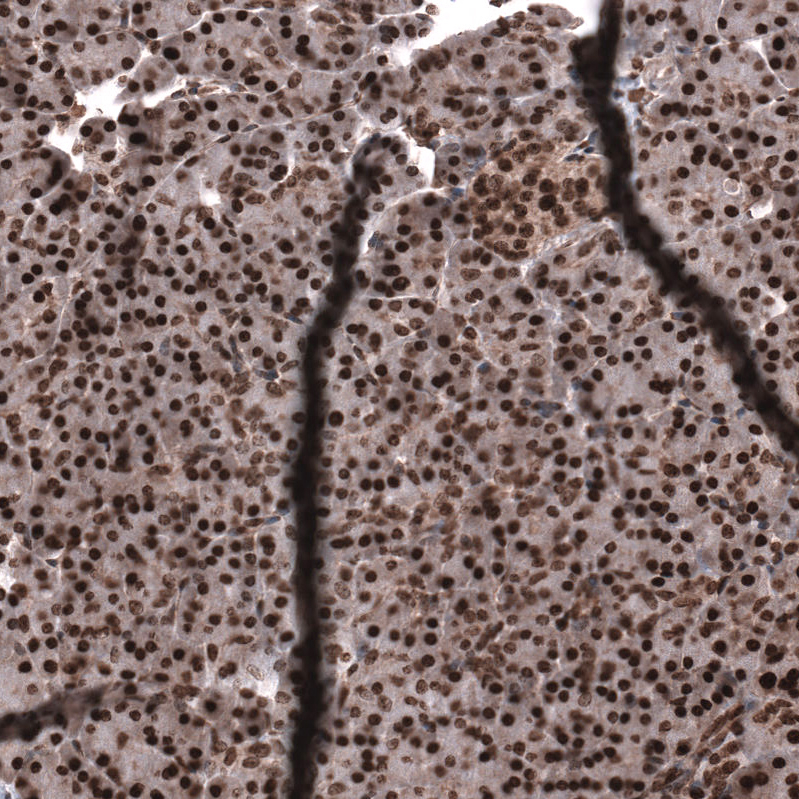

Immunohistochemical staining of human pancreas shows strong nuclear positivity in exocrine glandular cells and endocrine glandular cells.